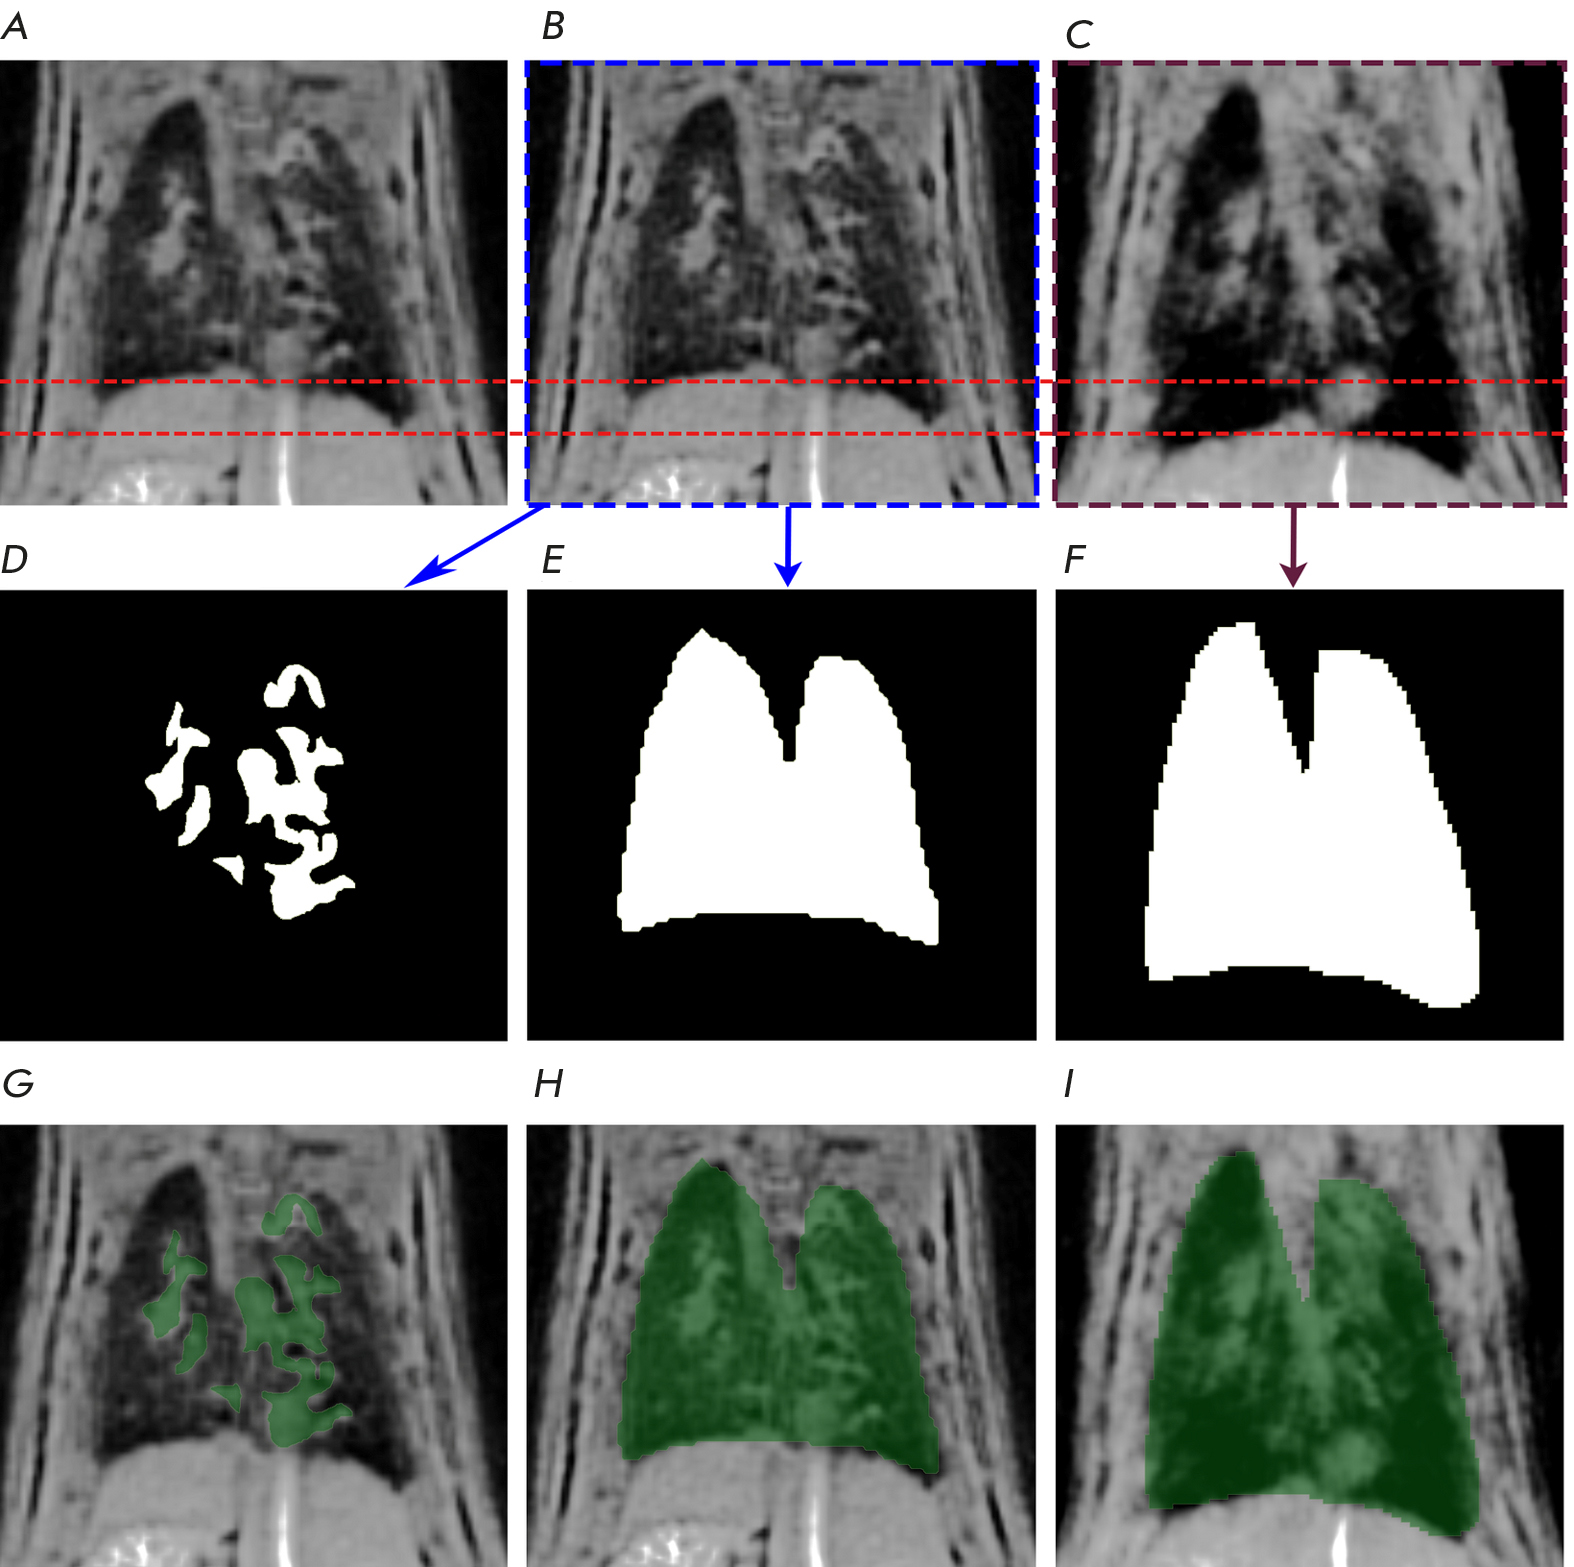

The results of MRI data processing for one of the rats are shown in Fig. 1.

Fig. 1. Pulmonary MR images of a randomly selected rat from the Saline group along with the corresponding lung and pathology masks. The data are presented only for one slice.(A) – initial MR image of the lungs;(B) – image of the expiration phase;(C) – image of the inspiration phase;(D) – pathology mask;(E) – expiration mask;(F) – inspiration mask;(G) – pathology mask overlaid on the initial MR image of the lungs;(H) – expiration mask overlaid on the image of the expiration phase;(I) – inspiration mask overlaid on the image of the inspiration phase